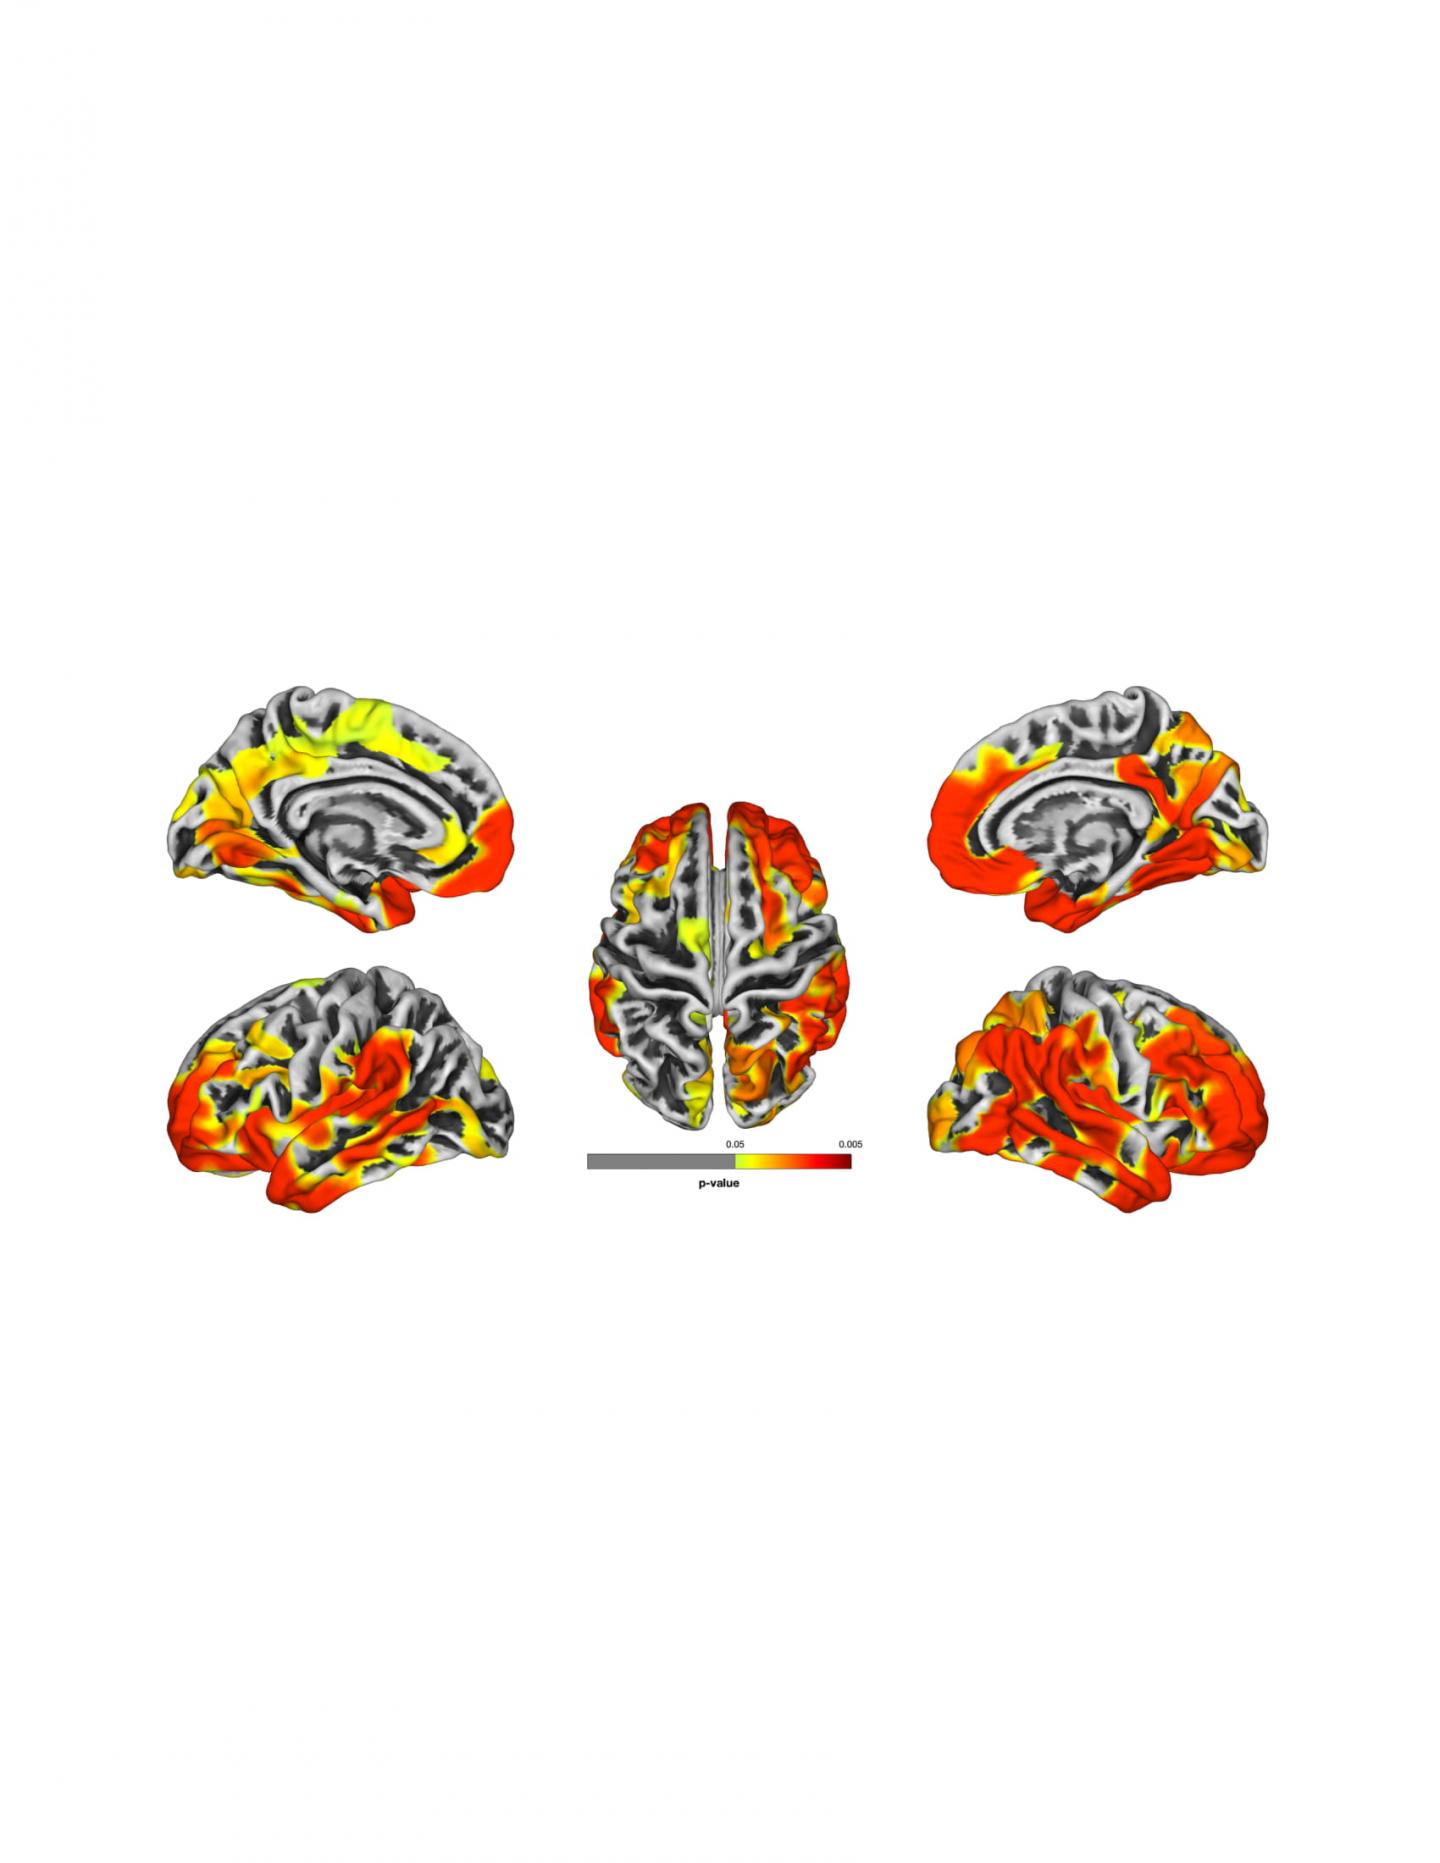

image: These brain images are a compilation of MRI results from WTC responders. The images show gray matter atrophy on the brain, with yellow and red areas revealing statistically significant atrophy compared to the normal population. Red areas show worse atrophy than yellow.

One study in Alzheimer's and Dementia: Diagnosis, Assessment and Disease Monitoring (DADM) shows that many responders with CI have reduced gray matter thickness in the brain consistent with neurodegenerative conditions and evidence their brain "age" is about 10 years older on average than the normal population. This research is in collaboration with scientists at the Icahn School of Medicine at Mount Sinai.

One study is the first to use MRI imaging to assess the brain matter of WTC responder patients with and without symptoms of CI. The goal of this study is to determine if WTC responders in their midlife have developed CI due to changes in their brain possibly caused by neurotoxins they were exposed to at Ground Zero. The age range of patients was 45 to 65 years, an age range where cortical atrophy is rare in the normal population.

Researchers measured the brain cortex, the area responsible for cognition. Cortical thickness is a consistent measure of brain atrophy commonly used in studies of patients with Alzheimer's and related dementias. Imaging revealed areas of the cortex are atrophied in many WTC patients with cognitive impairment, compared to control subjects.

"While there are many reasons for cognitive decline because of brain changes, the loss of gray matter in the brain is one of the most concerning and can be measured by cortical thickness," explains Sean Clouston, PhD, lead author and Associate Professor of Family, Population and Preventive Medicine and in the Program in Public Health. "We found a direct correlation between those suffering from cognitive impairment and cortical thickness, indicating a reduction in gray matter of the brain at levels consistent with neurodegenerative disease."

The overall amount of cortical atrophy in responders with CI was significantly more than responders who did not have CI symptoms, as well as to the general population based on normative data.

According to the authors, the MRI imaging revealed that cortical thickness was significantly reduced in 23 out of 34 cortical regions among those with CI. These included the frontal, temporal and occipital lobes. When compared to published data, both responders with CI and those without CI showed significant reductions in cortical thickness in seven regions in or near the temporal lobe potentially indicative of a population-level effect.

Dr. Clouston said that the level of reduction in the cortical thickness in many responders is similar to that in patients with dementia and is "a possible indicator of early stage dementia with possible early onset dementia likely to occur for a portion of these individuals at midlife."